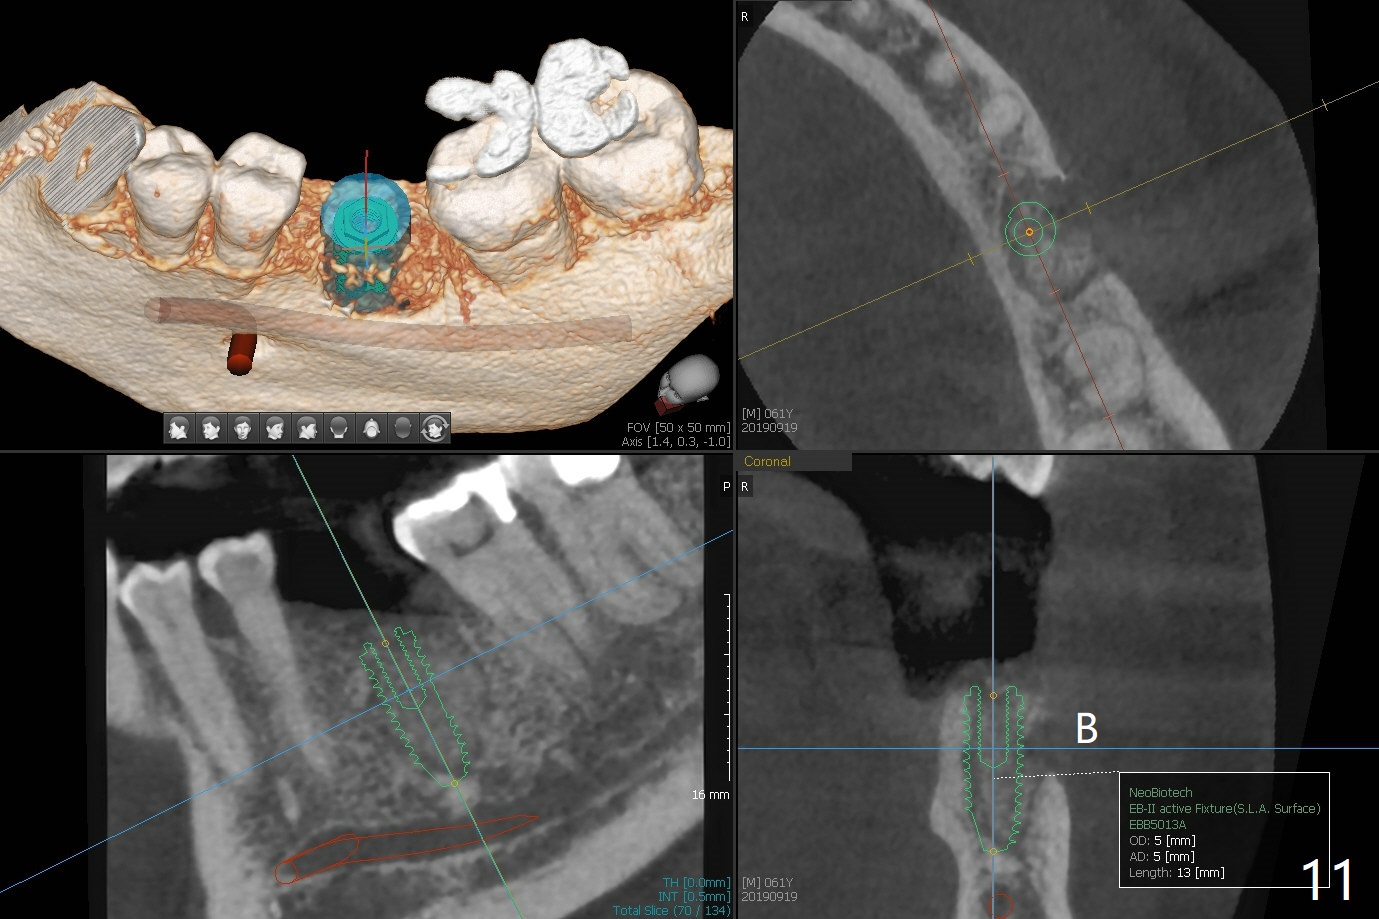

Extraction of the tooth #19 with large PARL (Fig.1,2) confirms the loss of buccal plate, but the crestal bone exists. After failure to place an implant in the middle socket with removal of the lingual septal bone, socket preservation is done with PRF and sticky bone (Fig.3). There is possibility to place a ~4 mm implant in the mesial socket (Fig.4). Or just drop a 5x11 mm Bicon Implant into the large socket, surrounded by sticky bone. When periodontal dressing is removed 18 days postop, the bone graft seems to remain to be "sticky" yellowish, while the granulation tissue has started to grow into the center of the socket from the previously buccal and lingual furcae (Fig.5 reddish). Granulation tissue seems to cover the bone graft (Fig.6), although there is smells when the periodontal dressing is removed. Bone height reduces nearly 3 months postop (Fig.7). The buccal plate collapses (Fig.8), but there seems no further bone loss 4 months postop (Fig.9). Because of buccal plate loss, an implant will be placed lingually with guide (Fig.10-12 green). Bone graft may be placed buccally after implant placement with probing.